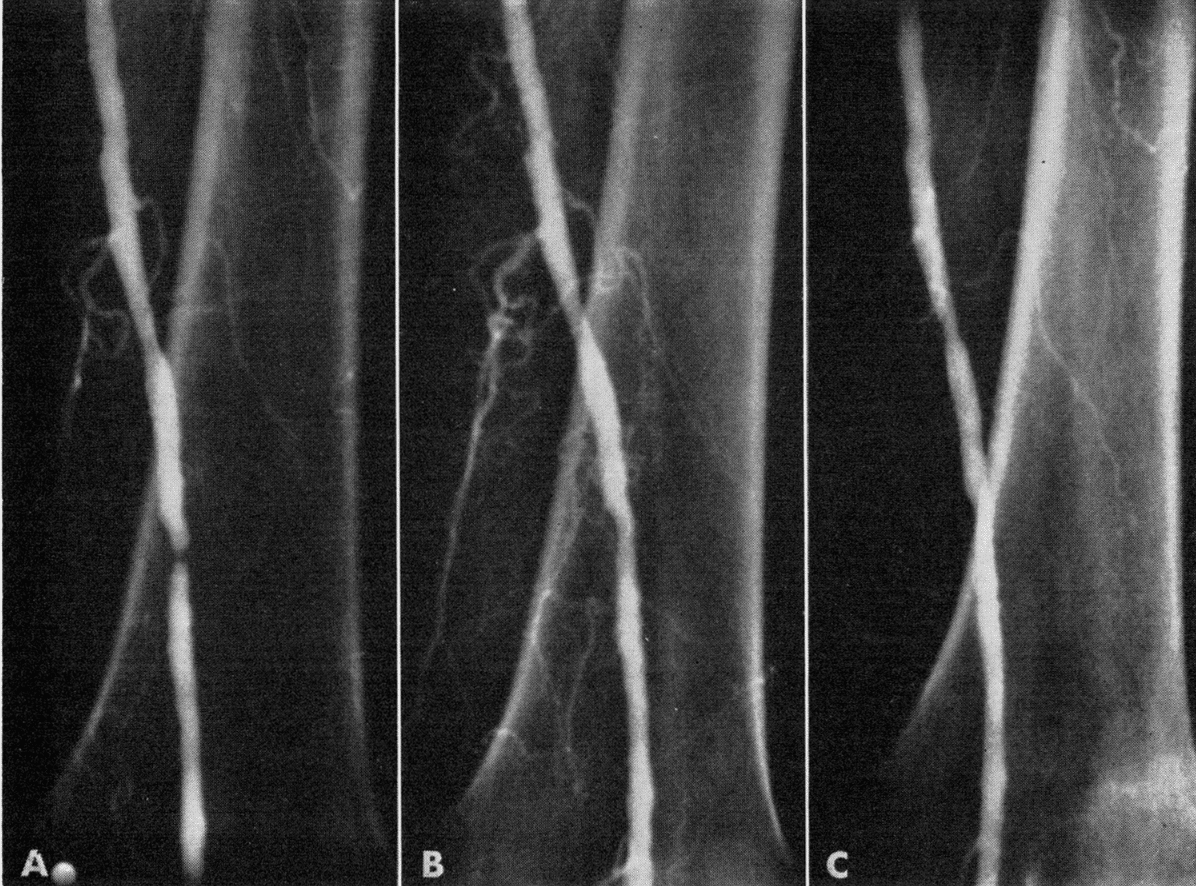

On 16 January 1964, Dotter and trainee Melvin Judkins performed the first intentional percutaneous transluminal angioplasty, using a wire guide and coaxial catheters to dilate a focal femoral lesion in Laura Shaw (aged 82), who had refused amputation; the limb reperfused immediately and the ulcer healed. This clinical “intraluminal operation” later gained wide surgical acceptance under the label “endoluminal surgery.”

- Dotter CT, Judkins MP. Transluminal treatment of arteriosclerotic obstruction. Description of a new technic and a preliminary report of its application. Circulation 1964; 30: 654-70